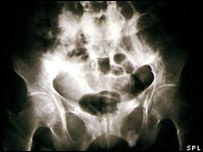

دانشمندان معتقدند که کمبود ویتامین دی در بدن ممکن است از عوامل درد مزمن در زنان باشد. براساس مطالعه ای که نتیجه آن در "نشریه بیماری های رماتیسمی" چاپ شده است این ارتباط در مورد مردان صادق نیست که نشان می دهد احتمال نقش آفرینی هورمون ها در این فرآیند وجود دارد. تیم محققان از "موسسه بهداشت کودک" در لندن گفت که مطالعات دیگری لازم است تا معلوم شود آیا قرص های ویتامین دی می تواند به عنوان عاملی علیه درد مزمن عمل کند یا نه. در بریتانیا از هر ده نفر یک نفر از دردهای مزمن رنج می برد. علل این موضوع به درستی درک نشده است و تا به امروز تمرکز مطالعات بر عوامل عاطفی بوده است. دکتر الینا هیپونن و همکارانش معتقدند که دست کم در زنان میزان ویتامین دی می تواند در برخی از موارد درد مزمن نقش بازی کند. ویتامین آفتاب ویتامین دی که برای سلامت استخوان ها ضروری است در اثر قرار گرفتن در معرض آفتاب در بدن تولید می شود و همچنین در ماهی های روغنی، زردی تخم مرغ و مارگارین یافت می شود. در این مطالعه 7 هزار مرد و زن 45 ساله به بالا در انگلستان، اسکاتلند و ولز شرکت کردند. در این میان کسانی که سیگار می کشیدند، کسانی که مشروب نمی خوردند، کسانی که اضافه وزن داشتند و کسانی که زیر وزن بودند همگی نسبت به میزان بالاتر درد مزمن شکایت داشتند. در میان زنان به نظر می رسید که میزان ویتامین دی در بدن در این زمینه نقش دارد. به گفته نویسندگان تفاوت ها در سبک زندگی یا عوامل اجتماعی، مانند میزان فعالیت جسمی و زمانی که فرد در فضای آزاد صرف می کند، این یافته را توضیح نمی دهد. زنانی که ویتامین دی بدن آنها از 75 تا 99 میلیمول در لیتر بود - یعنی مقداری که برای سلامت لازم است - کمترین نرخ ابتلا به درد مزمن را داشتند یعنی کمی بیش از 8 درصد. زنانی که ویتامین دی آنها کمتر از 25 میلیمول در لیتر بود بیشترین نرخ ابتلا به این درد را داشتند یعنی بیش از 14 درصد. کمبود شدید ویتامین دی در بزرگسالان می تواند به بیماری اوستیومالاسیا که با درد شدید استخوان همراه است منجر شود. اما محققان گفتند که اوستیومالاسیا توضیح دهنده این یافته نیست. دکتر هیپونن گفت که برای ارزیابی اینکه آیا قرص مکمل ویتامین دی می تواند به جلوگیری از درد مزمن کمک کند یا نه مطالعه دیگری لازم است. در همین حال وی توصیه کرد: "اگر من درد مزمن داشتم مسلما محکم کاری می کردم که به اندازه کافی ویتامین دی می خورم." کیت مک آیور از موسسه پژوهش درد در دانشگاه لیورپول اخطار داد: "خوردن دوز بالای قرص های مکمل ویتامین دی به عنوان راهی برای درمان درد مزمن می تواند به مسمومیت ویتامین دی و سطح بالای کلسیم خون منجر شود." اغلب مردم باید بتوانند تمام ویتامین لازم را از رژیم غذایی و همچنین گرفتن کمی آفتاب به دست آورند. | مطالب مرتبط ویتامین ث 'رشد سلولهای سرطانی را کند می کند'05 اوت، 2008 | دانش و فن مصرف ویتامین ها می تواند عمر را کوتاه کند17 آوريل، 2008 | دانش و فن ویتامین ث 'مانع سرماخوردگی نمی شود'21 ژوئيه، 2007 | دانش و فن 'کمبود ویتامین ب۱ در عوارض دیابت نقش دارد'08 اوت، 2007 | دانش و فن هشدار محققان ایرانی به زنان باردار در مورد مصرف آهن05 ژوئن، 2007 | دانش و فن خوردن سبزيجات از تصلب شرايين جلوگيری می کند18 ژوئن، 2006 | دانش و فن احتمال تاثير مثبت ويتامين 'بی 3' بر بيماری ام اس24 سپتامبر، 2006 | دانش و فن اختراع وسيله ای که به راه رفتن مبتلایان به ام اس کمک می کند30 آوريل، 2006 | دانش و فن | |||||||||||||||||||||||||||||||||||||||||||||||||||||||||||||||||||||||||||||||||||||||||||||||||||||||||||||||||||||||||||||||||||